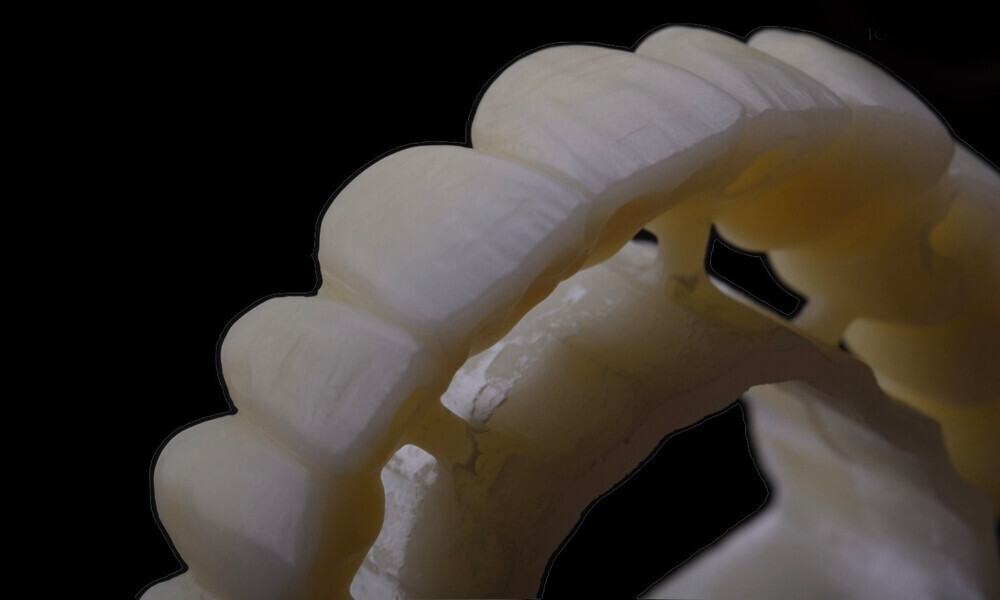

Employing a fully guided surgical protocol alongside a completely digital prosthetic workflow allowed for the precise design and milling of a PMMA provisional prosthesis (Figs. 34 & 35). The implant loading protocol implemented was immediate loading with equal distribution of forces across the entire prosthesis. The patient received the screw-retained provisional prosthesis on the same day. Temporary abutments (titanium copings) were placed on top of the screw-retained abutments. The spaces between the titanium copings and the provisional prosthesis were filled (Figs. 36–38). Any excess material was cut away, and the provisional prosthesis was subsequently polished to ensure a smooth finish (Fig. 39). The provisional prosthesis was then attached and securely fixed to the titanium copings to a 15 N cm torque (Fig. 40). Oral hygiene instructions were provided, and the occlusion was assessed (Figs. 41 & 42). A final control radiograph was obtained and confirmed that all parameters were within normal limits (Fig. 43).

Four months later, we proceeded with the final prosthetic procedure based on clinical and radiographic evidence confirming osseointegration. The case was completed using Straumann RevEX scan bodies for a full monolithic design with a completely digital workflow. First, an intra-oral scan of the opposite arch was taken, followed by an intra-oral scan with the screwed-in temporary abutments. An intra-oral bite scan and an intra-oral scan of the soft tissue with the screw-retained abutments in place were then taken. The reverse scan bodies were attached to the provisional prosthesis, which was scanned extra-orally. Next, the prototype and verification jig were designed, followed by the milling of the prototype and verification jig (Figs. 45 & 46).

During the next visit, the milled prototype and verification jig were tried in, and the design and manufacturing of the final prosthesis were completed (Figs. 47 & 48). The final abutment utilised was Variobase for bridge (Straumann), placed on top of the screw-retained abutments. The material chosen for the final prosthesis was monolithic zirconia (Figs. 49 & 50).